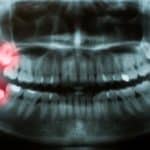

Many of us will develop our wisdom teeth, also known as third molars, at some point in our lives. Most commonly they start to show themselves in our teens but can make an appearance later in life… or perhaps never at all. However, these new molars can present a whole host of problems for us…